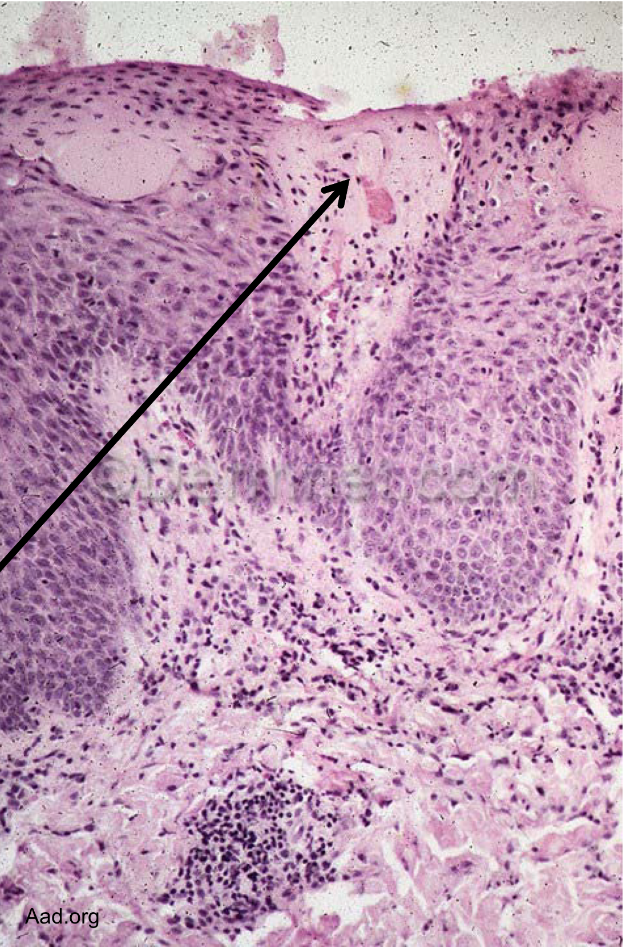

early psoriasis dominated by

erythematous lesions

secondary phase of psoriasis dominated by

plaques and scales

colors of psoriasis

Red- capillary dilation from inflammation

Silver- parakeratosis scale

psoriasis inflammatory response

CD4 TH1 and TH17, activated CD8 effector T → IL12, IFNy, TNF, IL17